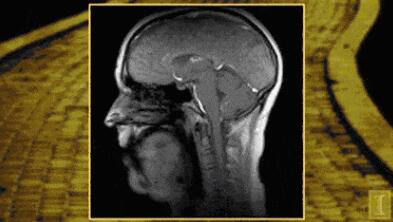

会厌,位于人体舌根部。急性会厌炎是喉科急重症之一,主要表现为会厌高度水肿。